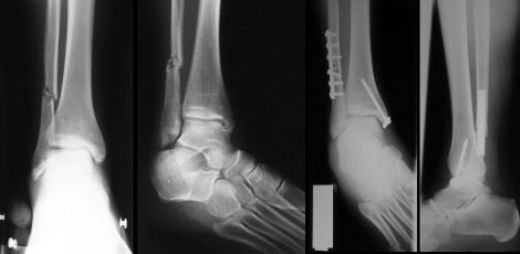

Tanı Yöntemleri Kemik çatlaklarının tanısı, hastanın şikayetleri ve fizik muayene ile başlar. Ancak, kesin tanı koymak için çeşitli görüntüleme yöntemleri kullanılabilir: